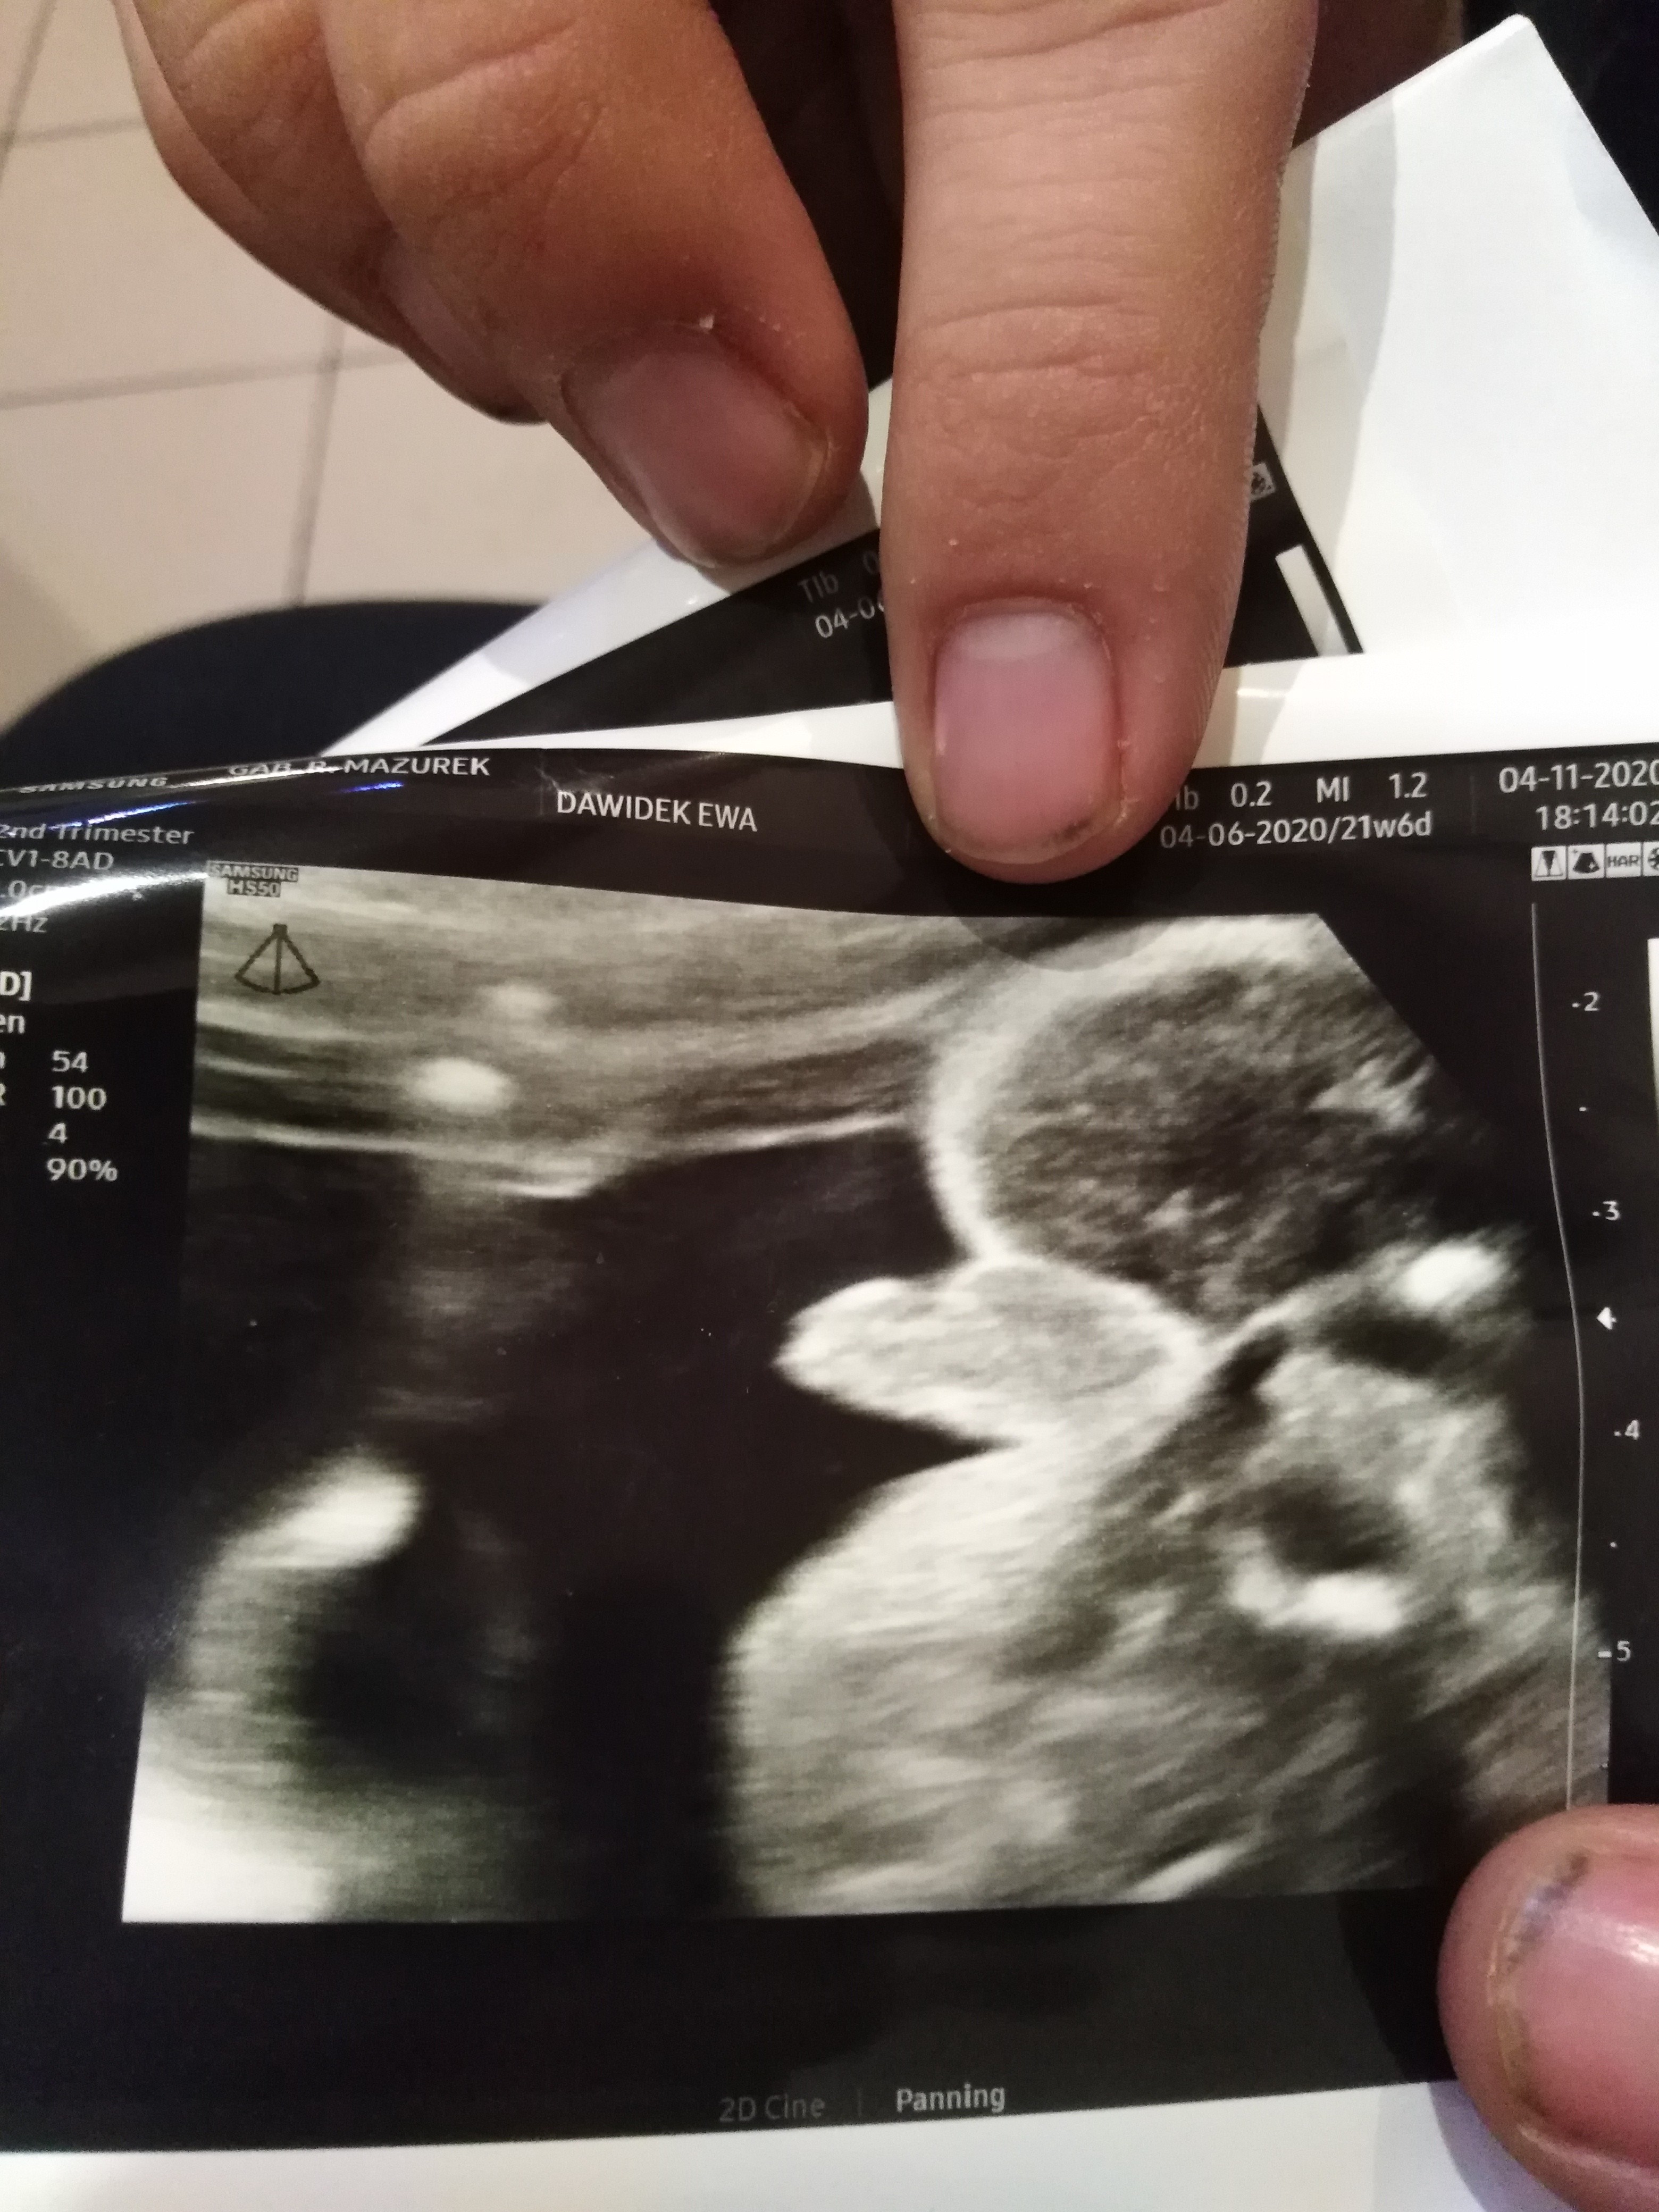

Ja mam dziś połówkowe 18:20 dopiero u mnie wg om 21t6d miałam mieć jutro ale lekarz do mnie zadzwonił i oznajmił że jest na kwarantannie i na szybko dziś znalazłam innego lekarza na szczęście się udało i w końcu się dowiem czy wszystko w porządku i kto tam mieszka😊 a co do pęcherza miesiąc się męczyłam z ciągłym sikaniem ale brałam 2x1 urosept i pomogło.

Już po usg połówkowym 480g wg usg 22 tydz wszystko jest w porządku i jednak miałam dobre przeczucie będzie chłopiec 😍

Załączniki

• IMG_20201104_200012.jpg

IMG_20201104_200012.jpg

2 MB · Wyświetleń: 136

• IMG_20201104_183828.jpg

IMG_20201104_183828.jpg

1,8 MB · Wyświetleń: 138